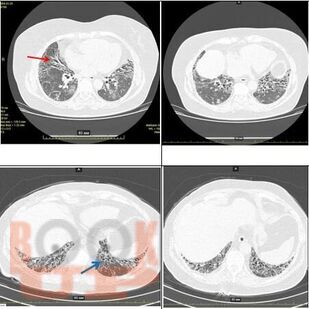

В данном учебном наглядном пособии изложена информация о рентгенологических особенностях поражений легких при различных интерстициальных заболеваниях. Использованы оригинальные снимки МСКТ, предоставленные коллективом авторов на основе клинических случаев легочного центра КГБУЗ ККБ. Пациенты с более редкими патологиями, которые не встречались у практикующих врачей КГБУЗ ККБ, представлены в атласе снимками из других ресурсов с указанием информационного источника.